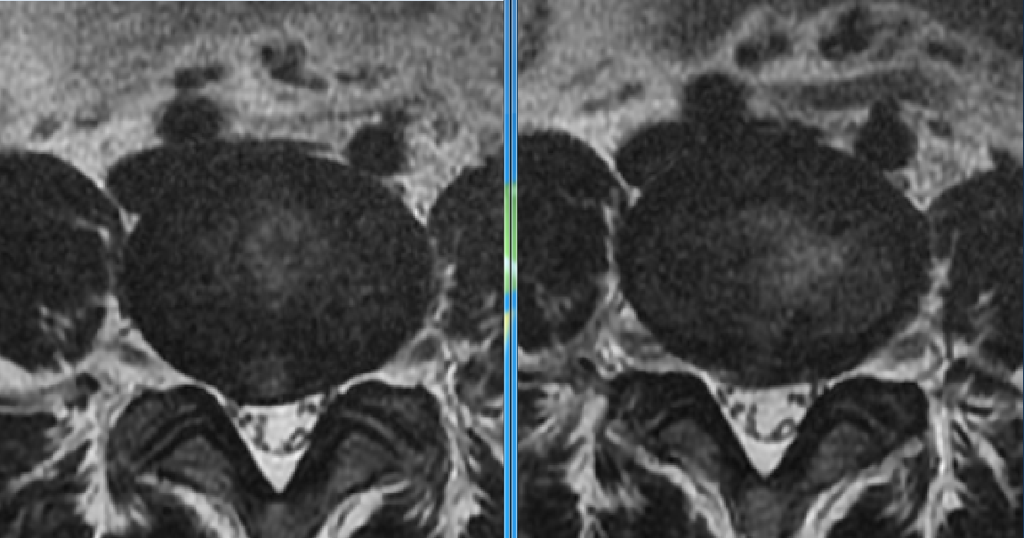

<왼쪽은 1차수술전, 오른쪽는 1차수술후>

일단 5곳 정도를 다녀본결과 제거가 덜 된 부분이 있고 재발한 부분도 있는 상태입니다. 이런 상태에서 어떤 수술을 해야할지 결정을 도와주세요.ㅠㅠ

-어린 나이에 현미경 수술은 너무 아깝다, 제거가 안 된 부분이 너무 명확히 보인다, 그런데 이미 다른 곳에서 한 번 했으니 이게 내시경으로 전부 제거될지는 장담못한다, 하지만 한 번 면죄부만 준다고 하면 시도해보겠다, 시도해보고 되면 좋은거고 수술직후 mri찍어보고 제거가 안되면 며칠의 텀을 두고 현미경으로 새로 하자, 내시경은 옆구리고 현미경은 등으로 하는거라 가능하다, 원한다면 바로 현미경해도 되긴한데 나이가 아깝다

저는 내시경을 한 번 더 도전해보고 싶습니다만.. 이미 한 번 했고, 두번째 내시경, 3번째 현미경하면 허리가 박살날까 싶기도 하고.. 내시경 도전해서 성공하면 또 좋은거니까 해볼까하다가도 제거됐다가 한 달안에 또 재발하면 어쩌나 싶고 .. 결정을 도와주세요..ㅠㅠ